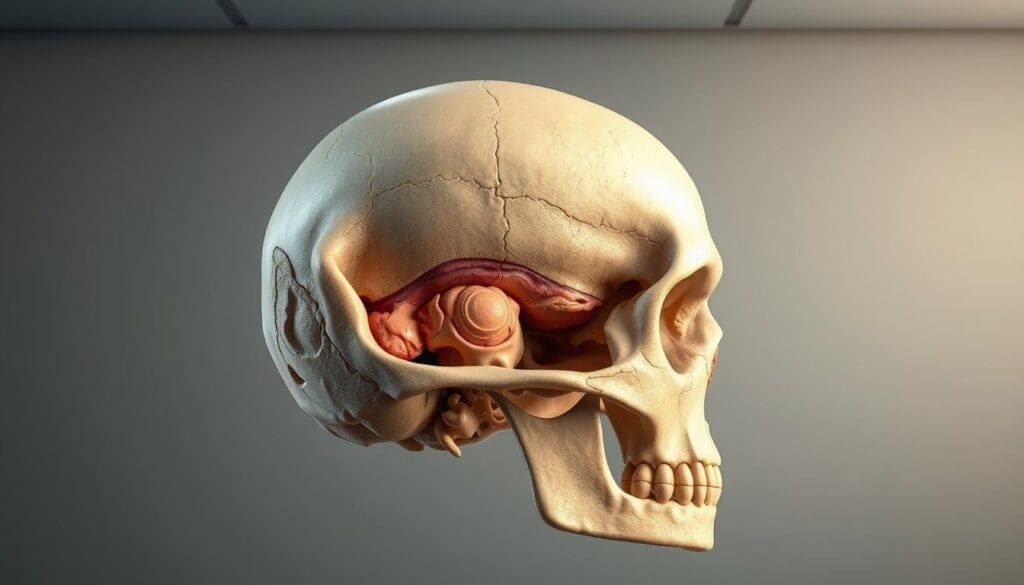

Anatomy of the Skull and Common Sites for Osteosarcoma

The human skull is made of several bones that fuse together. Osteosarcoma, a bone cancer, can affect it. Knowing the skull’s anatomy is key to treating this condition well.

The skull is a complex structure that houses the head’s skeleton. It’s made of many bones that join during growth.

Cranial Bones Affected

Osteosarcoma can happen in any skull part, including cranial bones. These bones form the brain’s home, the cranial cavity. Osteosarcoma here can cause a lot of harm because of its closeness to important brain parts.

Skull Base Involvement

The skull base is another common spot for osteosarcoma. It’s the floor of the cranial cavity, separating the brain from facial structures. Tumors here are hard to treat because they’re near vital blood vessels and nerves.